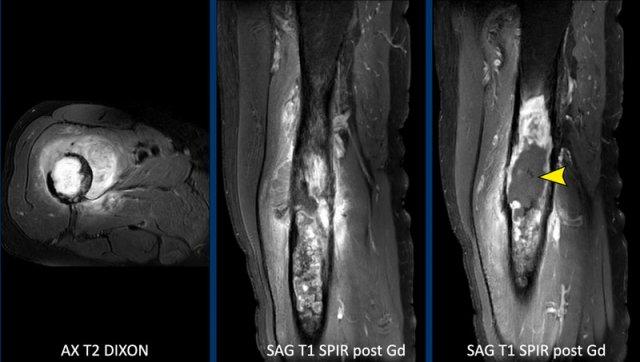

Hình ảnh

MRI xác nhận bản chất sụn của khối u với các nốt sụn tăng tín hiệu trên T2 DIXON cho thấy ngấm thuốc kiểu vách-nốt sau tiêm thuốc tương phản.

Tuy nhiên, cũng có phù tủy xương đáng kể ở phía gần (mũi tên đen) và phản ứng màng xương kèm ngấm thuốc (mũi tên trắng).

Kết luận

Các đặc điểm này rất đáng ngờ cho chẩn đoán u sụn ác tính độ cao.

Hình ảnh T1 axial xác nhận tình trạng lõm vỏ xương phía trước sâu chiếm khoảng 1/3 vỏ xương, tức là lõm vỏ xương mức độ rộng (> 10% chu vi khối u).

Cắt bỏ đầu trên xương đùi đã được thực hiện.

Chẩn đoán cuối cùng: sarcoma sụn độ II